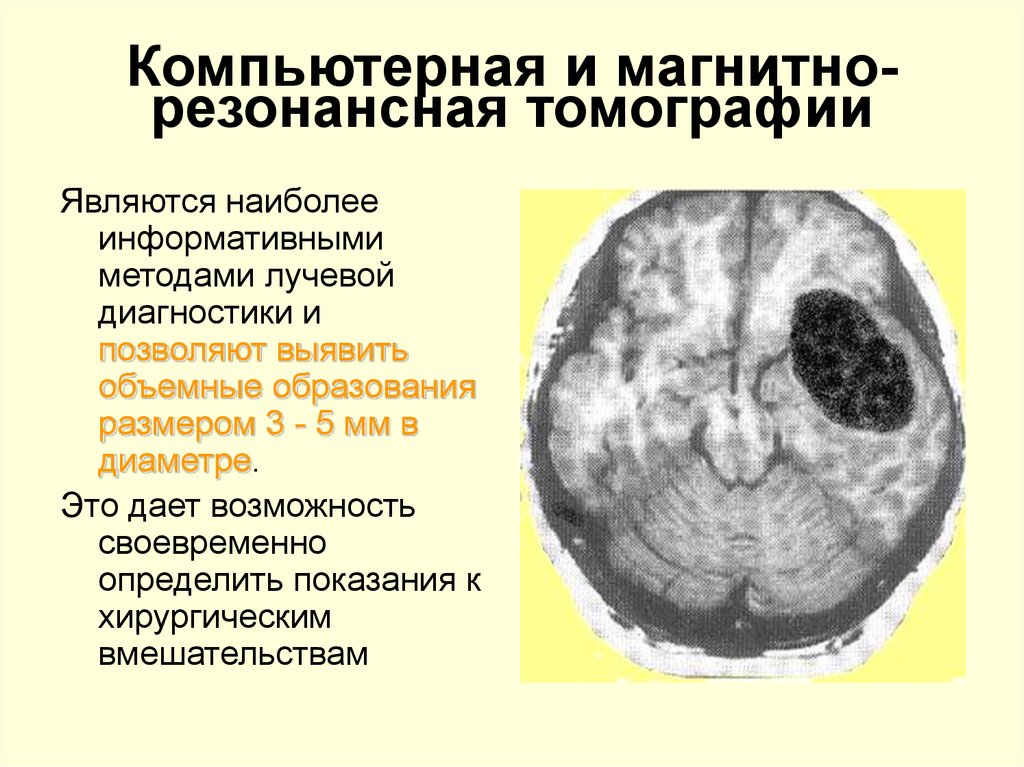

Опухоль головного мозга стадии. Опухоль головного мозга симптомы. Проявление опухоли головного мозга. Степени опухолей головного мозга. Методы исследования при опухоли головного мозга. Дополнительные методы исследования опухолей головного мозга. Диагноз кт с опухолью головного мозга. Дополнительные методы исследования при опухолях головного мозга.

Методы исследования при опухоли головного мозга. Дополнительные методы исследования опухолей головного мозга. Диагноз кт с опухолью головного мозга. Дополнительные методы исследования при опухолях головного мозга. Диагностика ра а желудка. РВК желудка дипгностика. Иагностика рада желудка. Методы диагностики в онкологии.

Диагностика ра а желудка. РВК желудка дипгностика. Иагностика рада желудка. Методы диагностики в онкологии. Опкхолльлголовного мозга. Новообразование в головном мозге. Злокачественная опухоль головного мозга.

Опкхолльлголовного мозга. Новообразование в головном мозге. Злокачественная опухоль головного мозга. Методы диагностики опухолей. Метод диагностики опухолей. Методы выявления опухоли. Этапы диагностики опухолей.